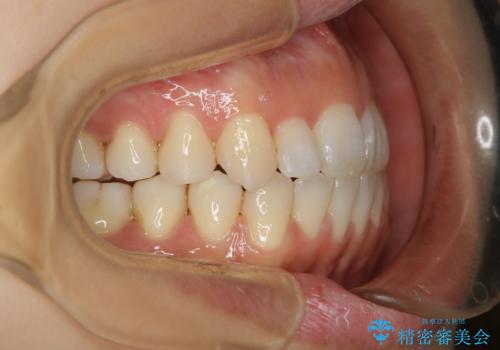

- ワイヤー矯正 審美装置

インビザラインの方法でも治せる患者様でしたが、希望によりワイヤー矯正となりました。

インビザライン治療を始めた後であっても使えないことが判明する患者様もいらっしゃいます。

当院であれば、そのような患者様の場合でも途中でワイヤー治療に切り替えて差し上げることが可能となります。